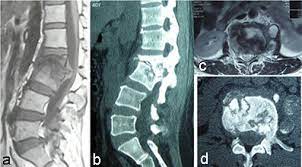

Untuk menegakkan diagnosis dan memastikan seberapa parah kerusakan tulang belakang, dokter akan merekomendasikan pemeriksaan penunjang, seperti Rontgen Xray, CT Scan, ataupun MRI.

Pada kasus spondilitis TB, MRI adalah pilihan terbaik karena lebih sensitif dibandingkan rontgen dan lebih spesifik dari CT-Scan. MRI bisa menunjukkan diagnosis cepat jika ada keterlibatan neurologis.